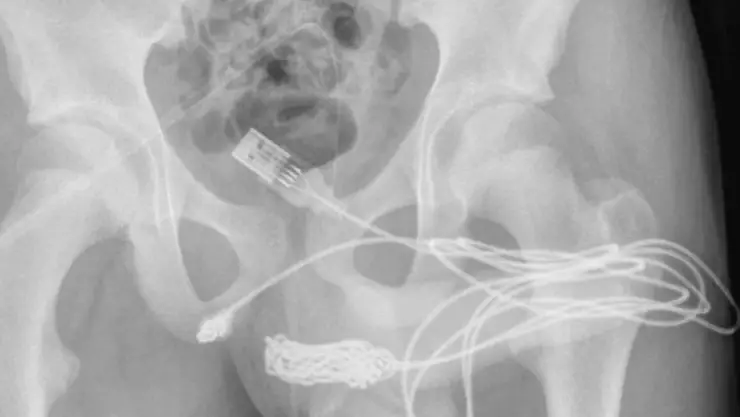

Los estudios de rayos X mostraron que los dos puertos del cable USB habían salido de la uretra, pero que la parte de en medio del cable se encontraba dentro de la uretra y se había enredado, por eso no podía sacarlo.